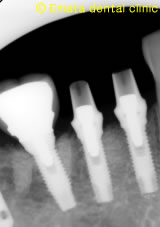

レントゲンでもインプラントのまわりの骨も安定しています。 |